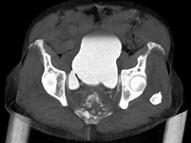

男,67岁,排尿困难1年余,加重1个月,请结合下列图片作出诊断 ( )A、膀胱结核B、膀胱炎C、输尿管囊肿D、膀胱结石E、膀胱憩室

问题 男,67岁,排尿困难1年余,加重1个月,请结合下列图片作出诊断 ( )

选项 A、膀胱结核 B、膀胱炎 C、输尿管囊肿 D、膀胱结石 E、膀胱憩室

答案 E